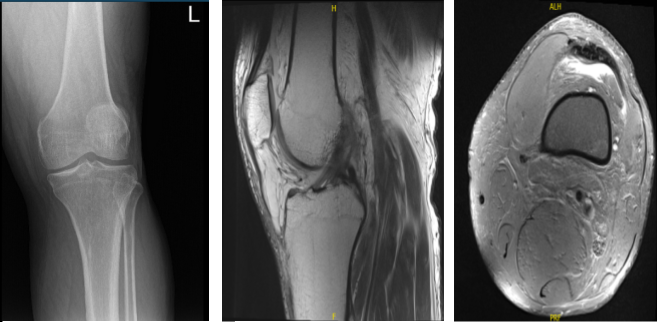

Xray presented no significant degenerative changes. Recommend a patient to take MRI. MRI results oblique flap tear in the posterior horn and body medial meniscus with associated para meniscal cyst measuring 8x3x3 mm.

Aside from this, it showed oblique tear in the body and posterior horn of the lateral meniscus. Also seen moderate knee joint effusion. Moderate bilateral popliteal cyst on C4. Focal chondral fissure in the lateral patellar facet.

X-ray Left Knee MRI-Left Knee